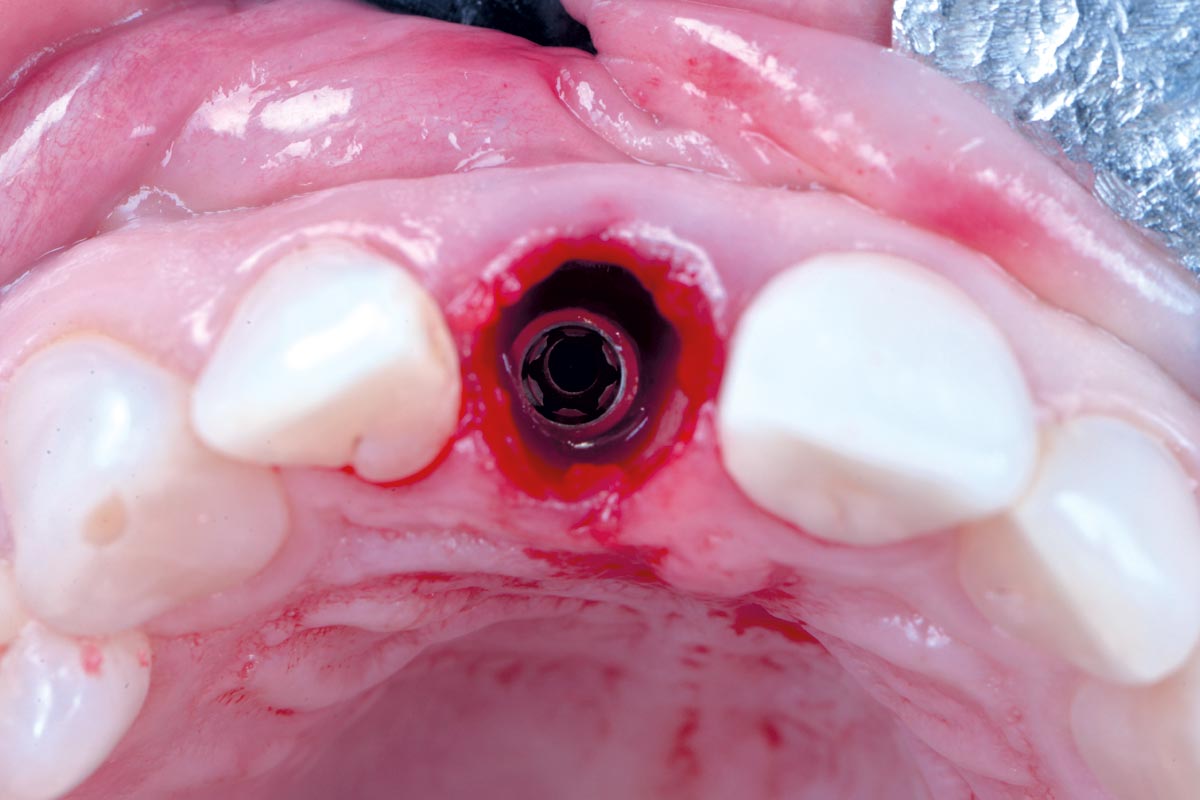

Covering of an immediately placed implant with permamem® - Prof. Z. Mazor

Immediately placed implant covered with permamem®. permamem® passively immobilized by sutures and intentionally left exposed to the oral cavity.